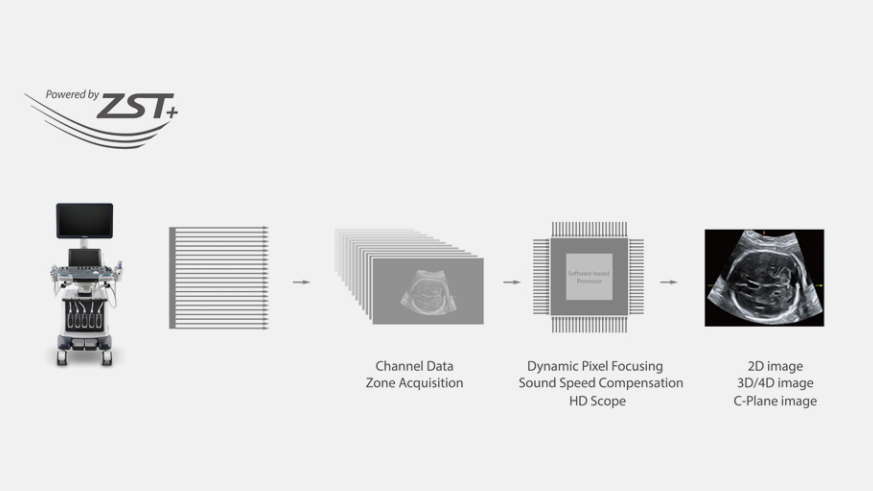

Since the company was founded, Mindray is continuously exploring new ways to improve diagnostic confidence. Powered by the most revolutionary ZONE Sonography? Technology, the ZST+ platform brings ultrasound image quality to a higher level by zone acquisition and channel data processing.

Thanks to the innovative, software-driven ZST+ platform, the Resona series is continuously evolving with the leading-edge technologies to meet the most challenging diagnostic demands in womenŌĆÖs health practice. More importantly, it is designed with the understanding that the wisdom of experts is always precious, and you need more intelligent partner for enhanced speed and confidence. Finally, Resona series with Zone Intelligence provides a total solution to help you with diagnostic confidence, efficiency, and standardization across different diagnostic challenges in todayŌĆÖs demanding and overburden hospital environment.